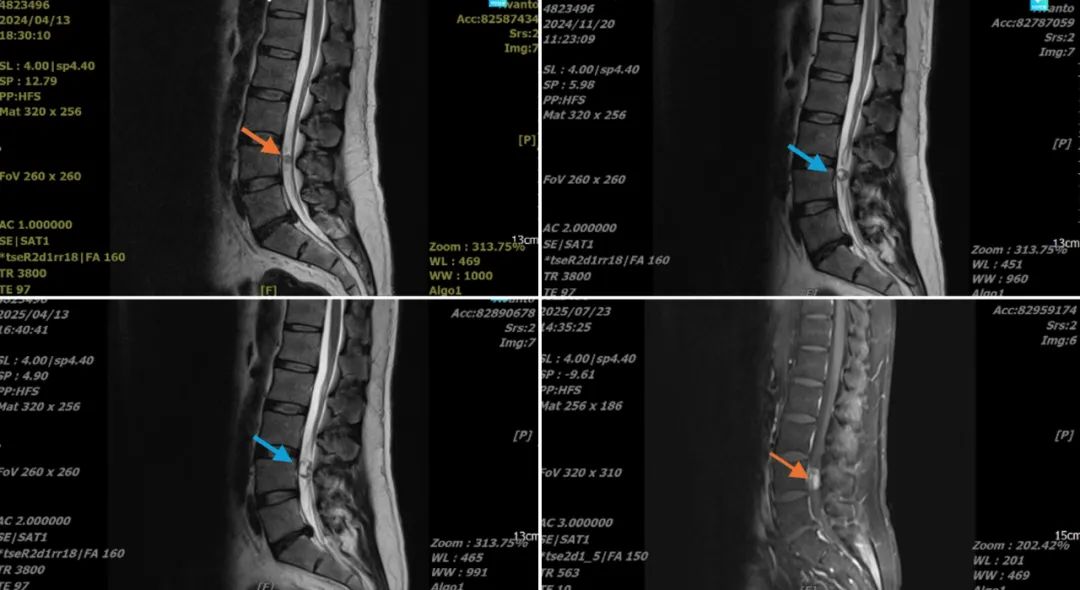

一年前,韩先生因腰部疼痛伴双下肢放射痛,于脊柱一病区门诊就诊。首诊主任医师苏小强详细了解其病史后,嘱其行腰椎MRI检查。检查结果提示,韩先生的病情比较特殊,不仅仅是腰椎间盘突出压迫神经根,在其硬脊膜内发现一块占位性组织,对周围神经有压迫。

一年时间里,韩先生因病痛先后5次住院,复查腰椎MRI显示,硬脊膜内的占位性病变在进行性增大。苏小强密切关注其病情变化,耐心解释,劝说患者接受手术治疗,韩先生却始终对手术有恐惧心理。

面对韩先生的复杂病情,王向阳组织全科进行详细术前讨论。结合详尽影像学检查明确该患者为L5-S1椎间盘突出压迫神经根及L4水平椎管内占位。医疗团队认为,手术中最大的难点是如何剥离肿瘤与局部神经组织的粘黏,迅速找准病灶,减少手术时间。